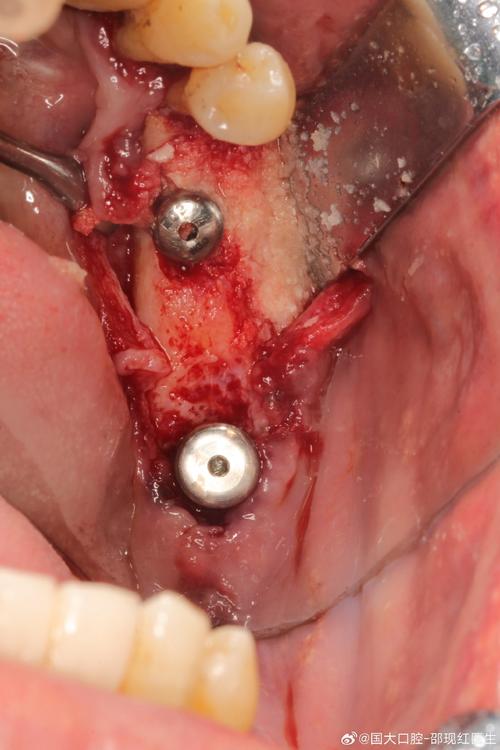

| 微创拔牙 | 使用微创拔牙挺挺松牙根,避免暴力敲击,尽量保留唇舌侧骨壁完整性。 | 若发现根尖炎症或骨破坏,需改为传统种植,彻底清创后再植入种植体。 |

| 种植体植入 | 按照术前设计方向植入种植体,扭矩需≥35Ncm(确保初期稳定性);植入后拍摄CBCT确认位置。 | 避免穿通牙槽骨侧壁,下颌后牙区需远离下牙槽神经管(距离≥2mm)。 |